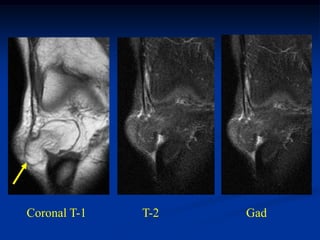

Case #1213

46 year male with

lymphangioma arm

Axial PD MRI

Another T-2 MRI

showing 2 lesions

Coronal T-2 MRI

vein

showing lymphangioma

next to cephalic vein